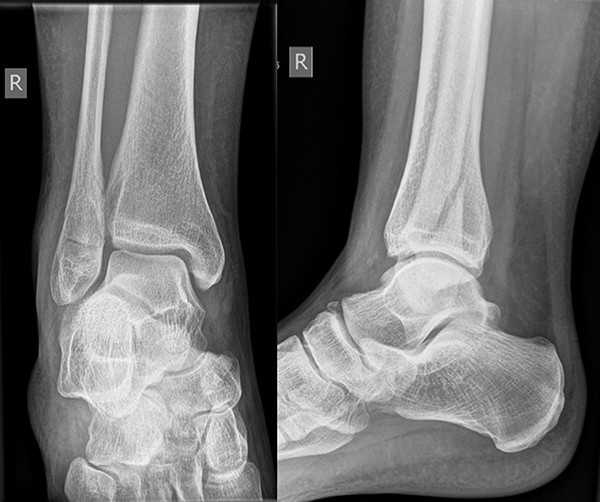

Die Standard-Röntgenaufnahmen des oberen Sprunggelenks bestehen aus drei Aufnahmen: der antero-posterioren Aufnahme (ap), der antero-posterioren Aufnahme mit Innenrotation des Unterschenkels von 20° („Mortise view“), sowie der streng seitlichen Aufnahme (siehe S2-Leitlinie Sprunggelenksfraktur). In der Röntgen-Bildgebung sollte neben den klassischen Frakturzeichen die Integrität der Syndesmose beurteilt werden. Dies erfolgt über die Beurteilung der Breite des lateralen und medialen Gelenkspalts („medial clear space“), des tibiofibularen Abstands 1cm oberhalb des OSG-Gelenkspalts („tibiofibular clear space“), bzw. der tibiofibularen Überlappung. Eine Verbreiterung des tibiofibularen Abstands über 5 mm oder die Erweiterung des medialen Gelenkspalts können Zeichen einer begleitenden Syndesmosenverletzung sein. (Abbildung 3) 6.